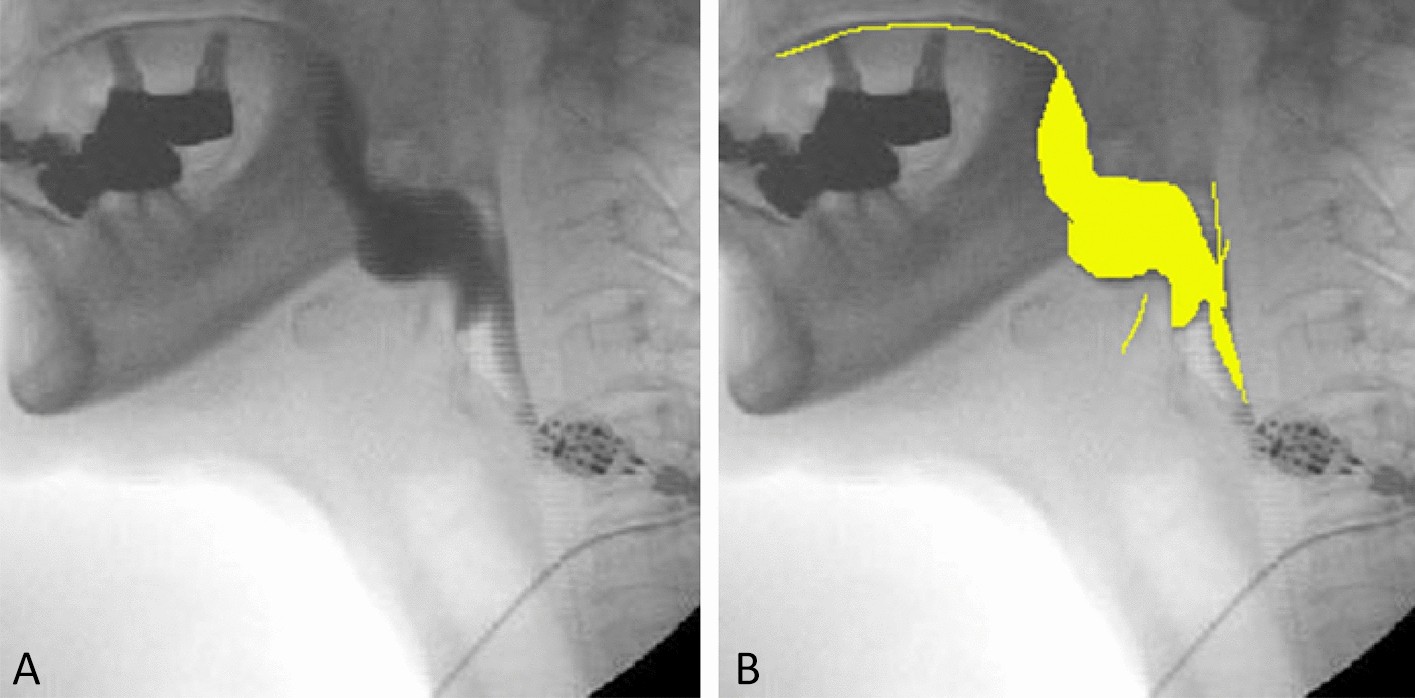

Annotation using training and verification datasets. (A) Original image. (B) Image in which contrast-enhanced bolus areas were colored.